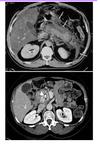

What are the white parts in the 2nd CT scan?

White parts in the 2nd CT scan shows calcium deposits (rok solid depositions) in the head of the pancreas

- Necrotic = if infected, many corresponding issues (black part on the CT scan shows bacteria producing gas in the infected pancreas)